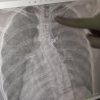

ELAZIĞ - Halk arasında 'Omurga Eğriliği' olarak bilinen skolyoz hastalığının teknolojinin gelişmesiyle son 10 yılda arttığına dikkat çeken Fizyoterapist Muhammed Barış, bu hastalığın çocuklarda erkek çocuklarına oranla kız çocuklarında 8 ile 10 kat daha fazla görüldüğünü kaydetti. Elazığ Mediline Hastanesi Fizik Tedavi Biriminde görev yapan Fizyoterapist Muhammed Barış, halk arasında 'omurga eğrilmesi' olarak bilinen skolyoz hastalığı hakkında istatistiksel veriler paylaşarak bilgi verdi.Literatürde yapılan çalışmalarda her 100 kişiden 2 ile 3'ünün omurga eğriliği olduğunu ama büyük çoğunluğunun bunun farkında olmadığını belirten Barış, bu hastalığın özellikle ortaokul ile lise çağındaki çocuklarda skolyoz taraması yapılarak tespit edilebileceğini bildirdi. Ayrıca omuz boylarının eşit olmaması nedeniyle tek taraflı çanta takan kadınlarda skolyoz gelişiminin daha fazla görüldüğünü gözlemlediklerini ifade eden Barış, hastaları klasik fizik tedavi yöntemleri metotların yerine başarı oranı yapılan çalışmalarda daha yüksek olarak belirtilen 'Schroth' terapi yöntemi ile tedavi edebildiklerini belirtti. Skolyoz hastalığı ve belirtileri hakkında bilgi veren Fizyoterapist Muhammed Barış, " Skolyoz, omurgada üç boyutta meydana gelen eğrilmelerin oluşturduğu bir deformitedir. Çok net bir şekilde evde yapılabilecek basit testlerle bu hastalığın varlığını anlayabiliyoruz. En çok hitap ettiğimiz, lise ve ortaokul grubu çocuklardır. Çünkü bu yaşta fark edildiği zaman skolyozun tedavisinde daha etkin sonuçlar alabiliyoruz. Özellikle çıplak bir şekilde çocuğunuza arkadan baktığınız zaman kürek kemiklerinde biri diğerine oranla biraz daha aşağıda duruyorsa,omuz boylarında eşitsizlik varsa, daha aşağı geldiğimiz zaman kalçada da bir eşitsizlik varsa bizlere başvurmalarını öneriyoruz. Bize en çok 'bir bacağım diğerine göre daha kısa hissediyorum,nefes alırken kaburgalarım bana batıyor,bir omuzum diğerine oranla daha aşağıda yada aynadan baktığımda iki tarafım eşit değil' gibi şikayetler ile geliyorlar. Bu şikayetlerle gelen hastalarımızı ilgili birimlerin uzman hekimlerine yönlendiriyoruz.Skolyoz tanıları alındıktan sonra fizik tedavi biriminde seanslarımıza başlıyoruz" dedi. "Tedavide kemik yaşı önemli" Skolyoz hastalığının istatistiksel verilerini paylaşan Barış" Yapılan çalışmalarda bu hastalık grubunda yüzde 2 ile 4 arasında bir oran var. Yani 100 kişiden 2'si veya 4'ü skolyoz hastası. Bunun büyük bir kısmı bu deformitenin farkında değil. Kız çocuklarında erkek çocuklarına oranla 8-10 kat daha fazla gözüküyor. Burada bizim için en önemli olan şey, kız çocuklarında menarj döneminde büyüme hormonu daha fazla salgıladığı için omurgada uzama meydana geliyor. Meydana gelen bu uzama mevcut skolyoz açısının artmasına sebebiyet veriyor. Skolyoz hastası bir kız çocuğunun mutlaka ilk reglinden hemen sonra bir fizyoterapiste danışması gerekiyor. Ondan sonraki 6 ay ile 2 senelik dönemde mutlaka kontrolümüzde olması gerekiyor" diye konuştu. Ebeveynlerin sorumluluklarına da değinen Barış, " Ebeveynlerin çocukların vücutlarını iyi analiz etmeleri gerekiyor çünkü çocukların bilinç düzeyi yüksek olmadığı için bir çoğu bu durumu fark edemiyorlar. Ebeveynler bu konuda çocuklarının kıyafetlerini çıkarttıktan sonra onları incelemesi gerekiyor. Özellikle çocuklarınızda omuz boylarının eşitsizlik ya da terminolojide 'gibozite' olarak adlandırılan ayakta durma pozisyonundan öne doğru eğilirken sırtta bir tarafta dışarıya doğru daha büyük bir çıkıntı oluşması ve kalça seviyelerinde eşitsizlik olduğunu gözlemlediyseniz ve böyle şikayetleriniz varsa hastanemize başvurabilirsiniz. Skolyozun sebebi belli değildir, doğuştan gelebilir ya da sonraki çevresel faktörlerle gelişebilir. Son yüzyılda gelişen bir tedavi metodu var ve bu tedavi ciddi başarı oranına sahip bir metot. 2017 yılında yapılan bazı çalışmalar neticesinde skolyoz üzerine 'Schroth' metodunun büyük fayda sağladığını skolyoz açısını azalttığını ve durdurduğunu biliyoruz. Bölgemizdeki ve ilimizdeki hastalar bu tedavi yöntemini uygulatmak için büyük şehirlere gitmek zorunda olduklarını söylüyorlardı ve daha çok Ankara, İstanbul ve İzmir'de tedavi görüyorlardı. Artık bu tedavi metodunu hastanemizde tarafımca uygulanıyor" diye bilgi verdi.